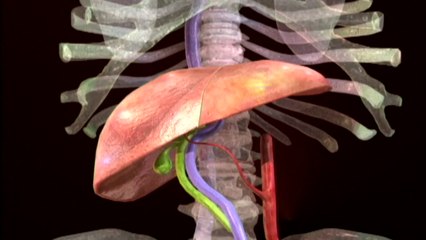

[앵커] 알츠하이머 치매는 현대인의 10대 사망원인 가운데 유일하게 예방이나 치료법이 없습니다. 그런데 국내 연구진이 물에 타 먹으면 알츠하이...